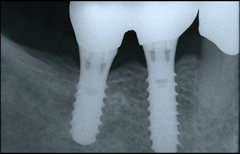

インプラントを埋入する部位の歯肉を開き、顎の骨にインプラントを埋入します。インプラントが骨にしっかり結合するまで約3ヶ月程度待ちます。 この間、必要に応じて仮歯を入れることもできますので、日常生活に差し支えありません。

人工歯を支えるためのアバットメント(支台部)をインプラントに接続します。 歯肉が治癒するまで約3週間待ちます。仮歯あり。